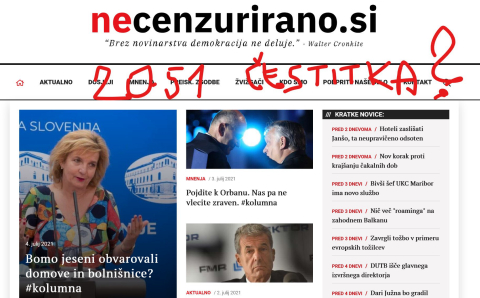

Resnica je prasica: medicinski fenomen ali ....?

Mestni politik sam širi v javnost zdravstvene dokumente...

1. julij 2021

Resnica je prasica: minilo je leto dni...virus pa je!?

Kranjski politik zanikal, demantiral ....ohhooho...kako znano!

1. julij 2021

Resnica je prasica: zarečeni kruh je (ne)užiten...

Virus politika Stevanovića....

1. julij 2021